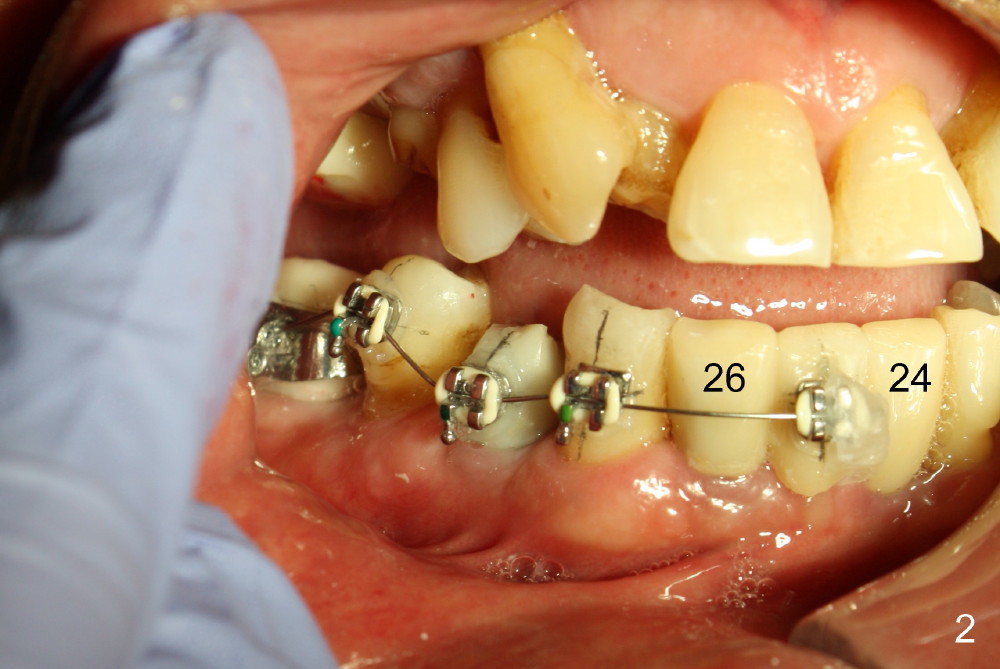

The main purpose of the 1st stage of ortho is to intrude the tooth #29 using implants at the sites of #28,30 as anchorages (Fig.1,2). If possible, intrusion of #27 is also needed. Since #24-26 is an implant supported bridge, one bracket in the pontic appears to be sufficient (Fig.2). Bracketing is also planned to extend to the lower left until #21 to distalize #22 (Fig.3). Supraeruption of #12 blocks the distalization. It appears that the supraeruption should be corrected after #13 implant placement (using the latter as an anchorage).